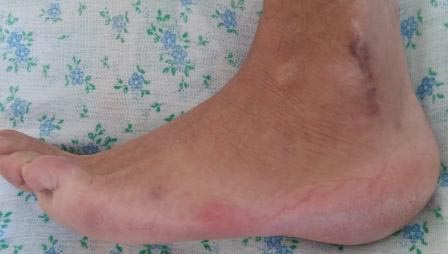

Вчера госпитализирован пациент 1970г.р., в ноябре 2014г, получил

о/перелом пяточной кости. в другой клинике произведена КДО аппаратом

Илизарова, после трех месяцев аппарат сняли, и больной начал наступать и

ходить, все это со слов больного (р-снимков нет.). Жалобы боль при

ходьбе, которая в динамике усиливается, об-но: деформация пяточной

кости, движение в г/стопном суставе почти в полном объеме, по медиальной

поверхности пятки рубец, плотно спаянный с костью.